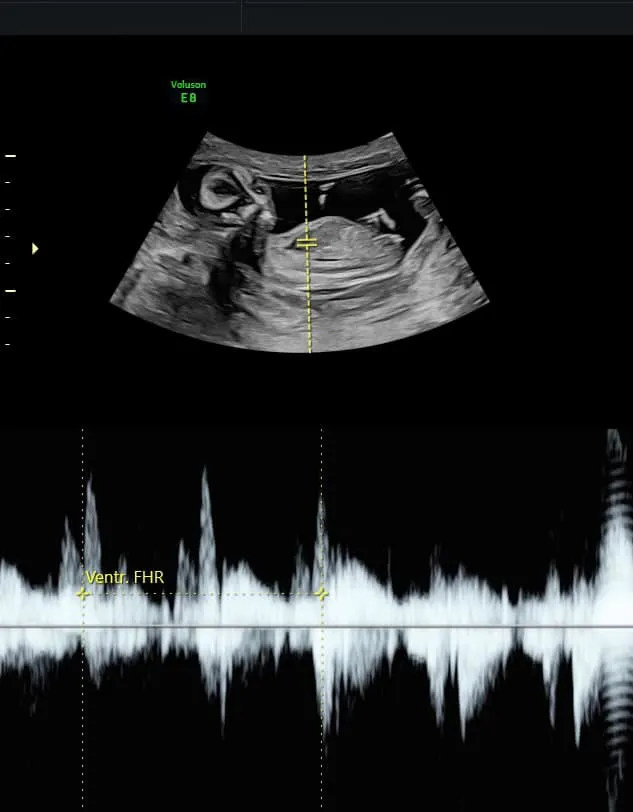

劉香慈開心表示,寶寶心跳聲好迷人。翻攝劉香慈臉書